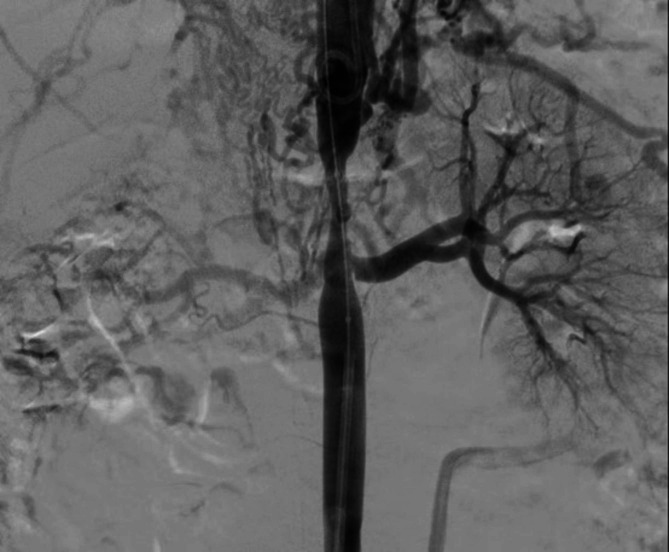

Case presentation: A 14-year-old male presented with a two-year history of refractory hypertension (peak:190/110mmHg) and exertional dizziness. Thoracoabdominal computed tomography angiography (CTA) revealed a focal coarctation (minimum luminal diameter: 4.2 mm, representing 70% stenosis) extending from the celiac artery origin to the superior mesenteric artery origin, without significant collateralization. Digital subtraction angiography (DSA)-guided balloon angioplasty (10 × 40 mm) resulted in a significant reduction of the transcoarctation pressure gradient from 45mmHg to 8mmHg, achieving normotension (120/80mmHg). At six-month follow-up, a 161% increase in aortic luminal diameter (to 11 mm) was observed, accompanied by complete regression of left ventricular hypertrophy (LVH), as evidenced by a decrease in interventricular septal thickness from 12 mm to 9 mm.

背景:先天性局灶性腹主动脉缩窄(CAAC)是一种罕见的血管畸形,常被误诊为中主动脉综合征(MAS)。管理CAAC的一个重大挑战,特别是在年轻人中,是在适应血管生长和发育的同时解决缩窄问题。本病例强调了多学科合作和成像引导的无支架球囊血管成形术在保持血管生长潜力方面的价值。病例介绍:一名14岁男性,有2年难治性高血压病史(峰值:190/110mmHg)和运动性头晕。胸腹ct血管造影(CTA)显示局灶性狭窄(最小管腔直径4.2 mm,狭窄70%),从腹腔动脉起源延伸至肠系膜上动脉起源,无明显侧支。数字减影血管造影术(DSA)引导的球囊血管成形术(10 × 40 mm)使血管收缩压力梯度从45mmHg显著降低到8mmHg,达到正常血压(120/80mmHg)。在6个月的随访中,观察到主动脉腔直径增加161%(至11mm),并伴有左室肥厚(LVH)的完全消退,室间隔厚度从12mm降至9mm。结论:无支架球囊血管成形术是治疗青少年CAAC的有效策略,既能立即缓解血流动力学,又能促进生长适应性主动脉重构。全面的主动脉造影对青少年难治性高血压的诊断和治疗至关重要。